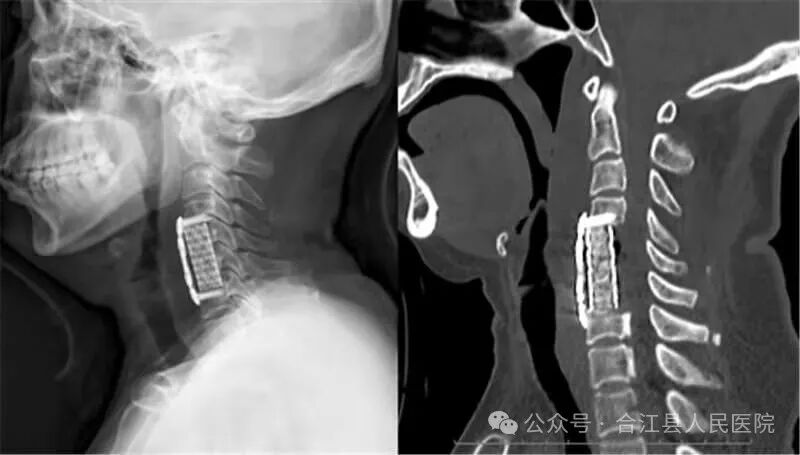

近日,我院脊柱外科为一名颈椎后纵韧带骨化(OPLL)伴椎管重度狭窄颈椎病患者成功实施了经前路颈5、6椎体次全切、后纵韧带骨化骨切除、椎管减压、钛网支撑植骨、前路钢板内固定术。

术前

入院后完善颈椎X线片、CT、核磁共振、血生化等各项检查,诊断为颈椎后纵韧带骨化(OPLL)伴重度颈椎管狭窄、脊髓型+神经根混合型颈椎病。

图片

术后